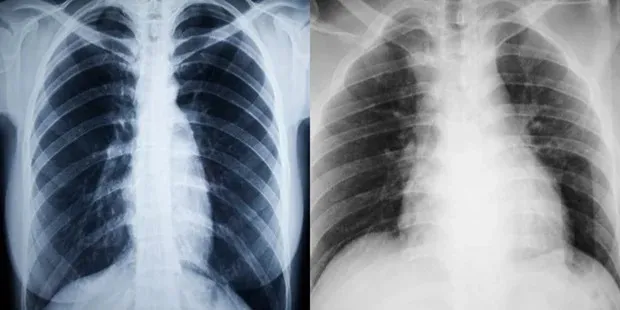

Tönkreteheti a tüdődet a Covid – egy friss tanulmány szerint erre az elég ijesztő szövődményre lettek figyelmesek a szakemberek, ami tulajdonképpen az egész szervet hazavághatja. Bár kevésbé meglepő, hogy a támadás a tüdőt érinti, az viszont megdöbbentően hangzik, hogy a neve konkrétan: post-Covid-19 fibrózis.

A post-Covid-19 fibrózis a Covid-19-tüdőgyulladás és ARDS (amikor a tüdőben lévő apró, rugalmas légzsákokban folyadék halmozódik fel, mely megakadályozza, hogy a tüdő elegendő levegővel teljen meg) egyik gyakori szövődménye. Becslések szerint ez a Covid-19-fertőzött, kórházban kezelt betegek egyharmadánál fordul elő – írja a COVID1001.hu.

A tüdőfibrózis során krónikus gyulladás indul el a tüdőszövetben, a léghólyagocskák és hajszálerek között, amely végül a kötőszövet felszaporodásához vezet, ezzel csökkenti a légző felületet. Lappangva kezdődik. Eleinte terhelésre, később nyugalomban is jelentkező nehézlégzés, száraz köhögés figyelhető meg. A légzés szaporává, felületessé válik. Sokszor jelentkezik mellkasi fájdalom, és ahogy telik az idő, a tünetek egyre súlyosabbak lesznek, az ajkak elkékülhetnek, a körmök óraüveghez, az ujjak dobverőkhöz hasonlókká válhatnak. Sokszor előfordul fáradékonyság, fogyás és láz.